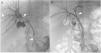

Un varón de 51 años de edad fue evaluado por ictericia obstructiva asociada a una dispepsia leve. El paciente tenía una historia médica regular, y la examinación física no reveló hallazgos significativos salvo por la ictericia. Los resultados de laboratorio mostraron enzimas hepáticas alteradas (bilirrubina total 20.1mg/dl, bilirrubina directa 18.8mg/dl, AST 53U/l, ALT 144U/l, GGT 386U/l y ALP 203U/l). Por medio de una tomografía computarizada (TC) y una subsiguiente colangiopancreatografía por resonancia magnética (CPRM) se demostró la presencia de una masa hiliar de 1.2cm, lo que constituía una estenosis hiliar y oclusión del tracto biliar y dilatación del mismo en el área intrahepática (fig. 1), lo cual sugirió el diagnóstico de colangiocarcinoma hiliar (Bismuth-Corlette II). La colangiografía percutánea para el drenado biliar interno-externo confirmó la contracción hiliar (fig. 2A); una colangiografía realizada 10 días después mostró su normalización (fig. 2B). El paciente se sometió a colangioscopia, confirmando hilio biliar normal (fig. 3), y se tomaron biopsias endobiliares por medio de fórceps en la misma sesión. La evaluación histopatológica reveló infiltrado celular inflamatorio crónico transmural sin signos de malignidad. La tinción inmunohistoquímica mostró células plasmáticas IgG4 positivas (figs. 4A y B). Seis meses después se confirmó un árbol biliar normal por medio de una CPRM (fig. 5).